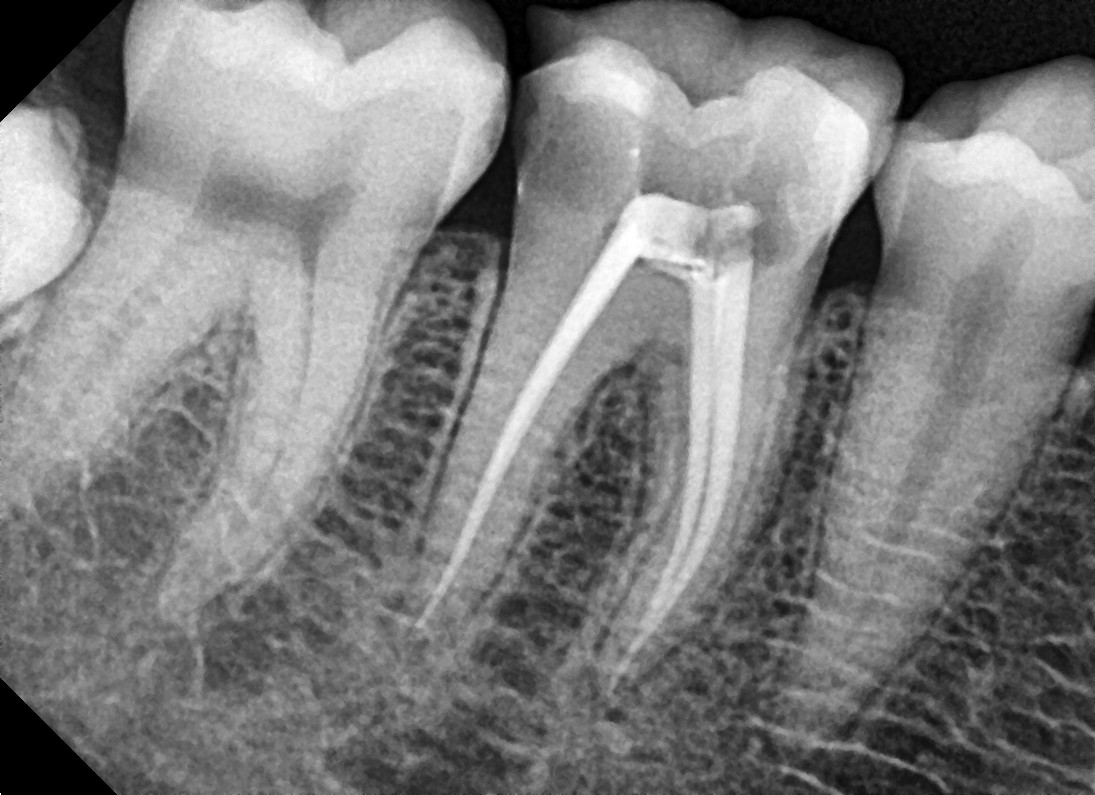

• Measurements of the length of the root canal is noted and take x-rays to confirm the length. Ensuring that the entire length of the root canal is cleaned.

• Obturation: Filling the root canal

• Once the bacteria and infection are under control (no more signs and symptoms of soreness or discomfort from the tooth), the root filling can be done.

• Irrigate the tooth with antibacterial solutions, dry the tooth, Gutta Percha (rubber points) should be placed into the root canals.

• Once the Gutta Percha is placed, a temporary filling on the tooth or a permanent filling on the tooth can be placed.